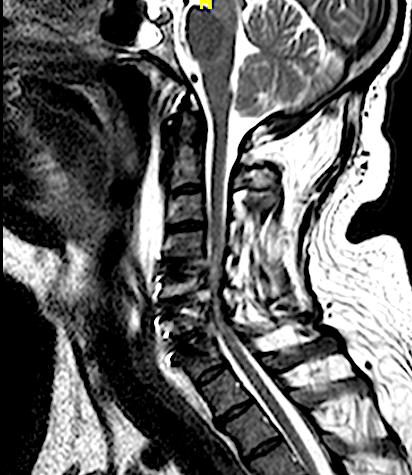

El paciente presentó a las 24horas un agravamiento de la paresia C7 derecha indolora, sin cambios en el puntaje (EMS) de su mielopatía, por lo que se decidió realizar una RM cervical urgente.

El resultado de la RM cervical planteaba dudas si era necesario o mandatorio realizar una descompresión posterior complementaria. Sin embargo, los parámetros clínicos no sugerían una compresión medular: la evolución lenta a la mejoría de su paresia, la ausencia de progresión de su mielopatía y la ausencia de dolor resultaron determinantes para que se adoptara una actitud conservadora. El paciente fue dado de alta (en plena pandemia de covid) y la evolución fue buena a pesar de que no pudo completar la rehabilitación. Se realizó nueva RM y RX cervical a los seis meses que resultó mucho más concluyente.

RM postoperatorio